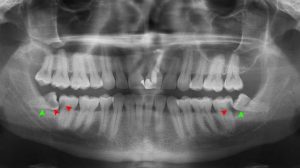

متخصص ارتودنسی شما در بررسی های اولیه و با کمک گرفتن از تصاویر رادیولوژی تشخیص می دهد که آیا ضرورتی برای کشیدن دندان مولر سوم از دهان وجود دارد یا نه . گاهی شلوغی و ازدحام دندان ها به قدری زیاد است که متخصص ارتودنسی شما چاره ای جز خارج کردن دندان مولر سوم از دهان شما ندارد .